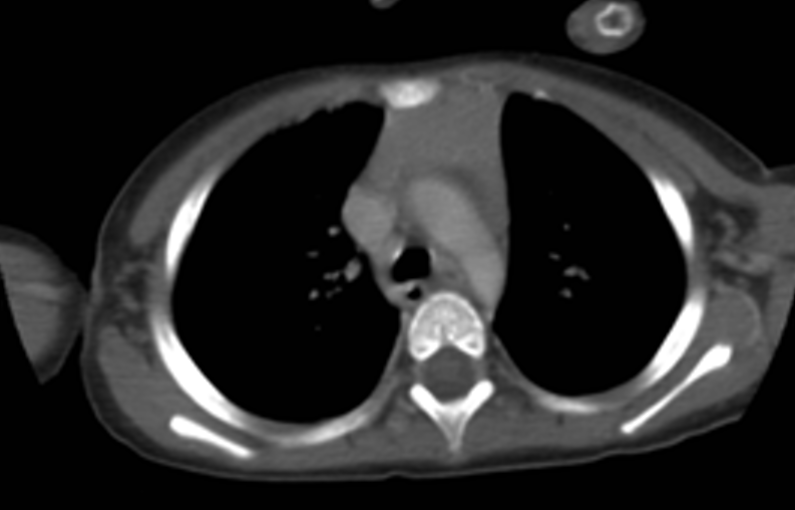

【109-2 醫學(四) 第74題】2歲女童因咳嗽就醫,由於胸部X光顯示縱膈腔變寬,因此在接受對比劑注射後,接受電腦斷層掃描檢查如圖,在主動脈弓之前可見明顯軟組織,其最常見原因為何?

詳解

破題關鍵

這題的關鍵在於病患的年齡(2歲女童)和影像學發現(前縱膈腔軟組織),在兒童時期,前縱膈腔最常見的軟組織就是正常的胸腺。

選項拆解